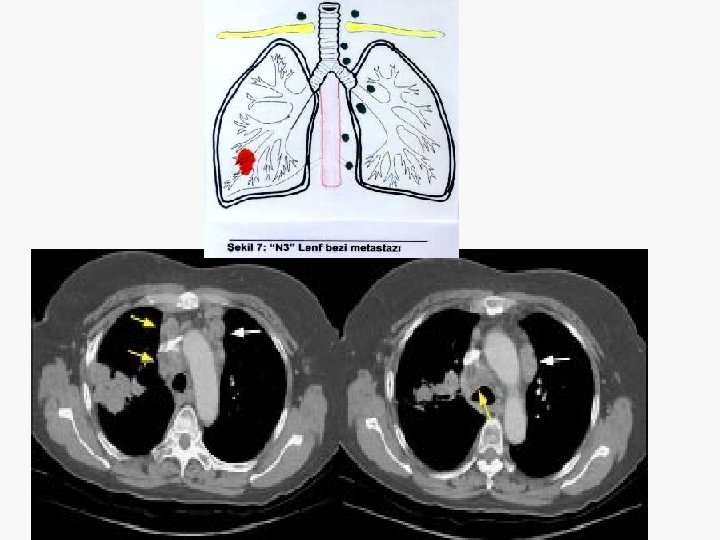

Evreleme EVRE 0 : Tis N 0 M 0 EVRE IA : T 1 N 0 M 0 EVRE IB : T 2 N 0 M 0 EVRE IIA : T 1 N 1 M 0 EVRE IIB : T 2 N 1 M 0 T 3 N 0 M 0 EVRE IIIA : T 1 -3 N 2 M 0 T 3 N 1 M 0 EVRE IIIB : T 4 N M 0 T N 3 M 0 EVRE IV : T N M 1

İnvaziv evreleme (1) BT’de LAP pozitif operabl olgularda mediastinoskopi zorunludur. – Servikal mediastinoskopi ile 2 R, 2 L, 4 R, 4 L, 7 (anterior) ve 1. ile 3. istasyonlara ulaşılabilir. – 5 ve 6 numara için genişletilmiş mediastinoskopi ya da torakoskopi gerekir. – 7 (posterior), 8, 9 numaralar için torakoskopi gerekir. – TTİİA, TBİİA, mediastinoskopiye alternatiftir, ancak negatif sonuçlar metastazı dışlamaz.

İnvaziv evreleme (2) BT’de LAP negatif operabl olgularda mediastinoskopi opsiyoneldir. – Cerrahi düşünülen Pancoast tümörlerde ve santral tümörlerde yapılmasında yarar vardır. – Periferik tümörlerde ihmal edilebilir. – Sol üst lob tümörlerinde genişletilmiş mediastinoskopi ya da torakoskopi gerekir.